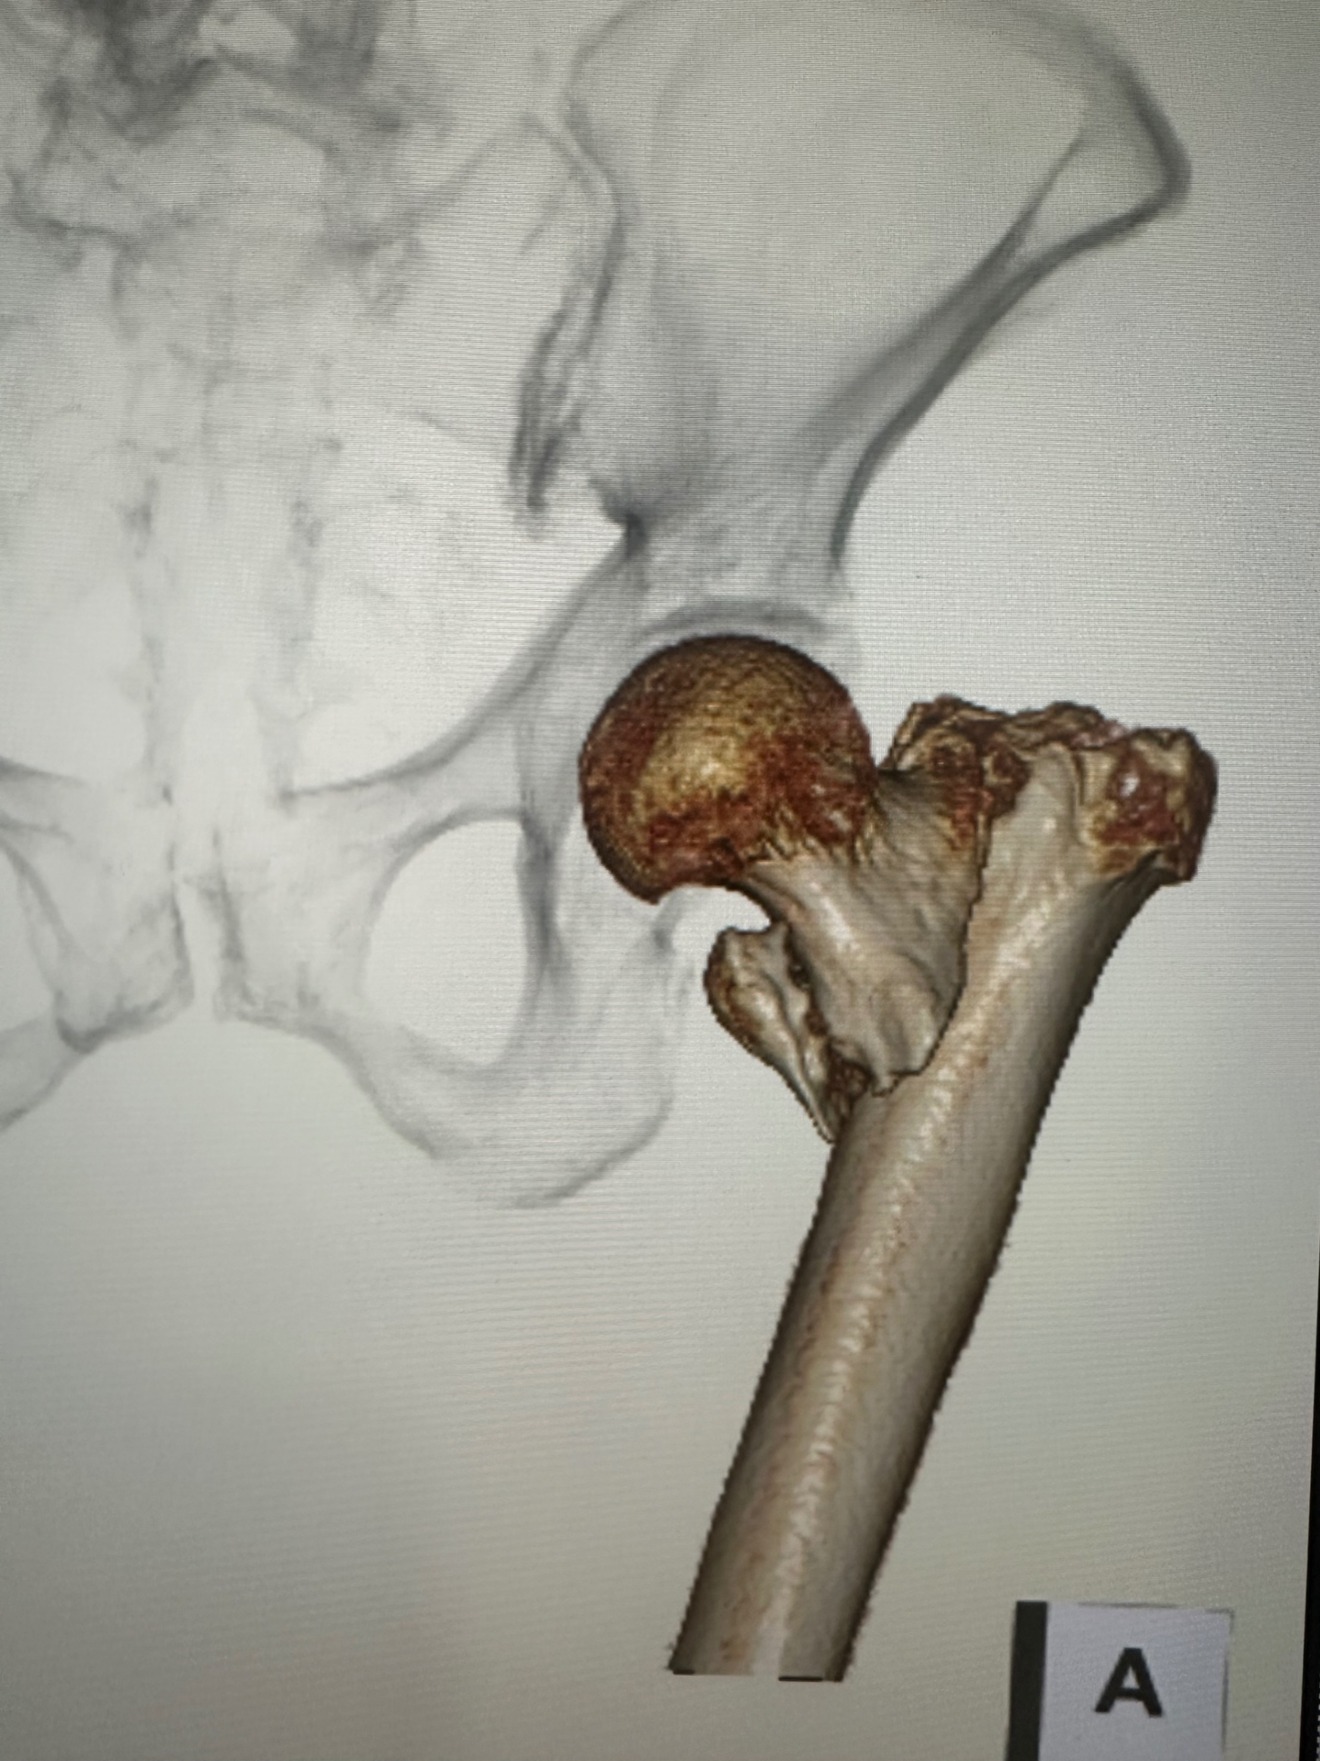

å€§è ¿éªšè¿äœéšéªšæ(倪ããã®ä»ãæ ¹ãè¡é¢ç¯ã®éªšæ)

転åã«ããèã®ä»ãæ ¹ãæããçã¿ã§æ©ãããšãã§ããªããªããŸãã

æ²»çã¯æè¡ãããªããã°æ©ãããšã¯ã§ããªããªã£ãŠããŸããŸãããŸãæè¡ãããŠãå€ãã®æ¹ãæ©è¡èœåãäœäžããŠããŸããŸããïŒå

éãæ©ãããšãã§ããªããªããæãæ©è¡åšãå¿

èŠã«ãªã£ããããããã§å¯ãããã«ãªã£ããïŒ

ãããã®éªšæãèµ·ãããšå ã«è¿°ã¹ãããã«åããªããªããŸããå Žåã«ãã£ãŠã¯æ©è¡èœåã®äœäžã«ããèªå® ã§ã®ç掻ãå°é£ãšãªãããšã§ããã®ãŸãŸæœèšã«å ¥æããããšã«ãªãã±ãŒã¹ãå°ãªããããŸããã